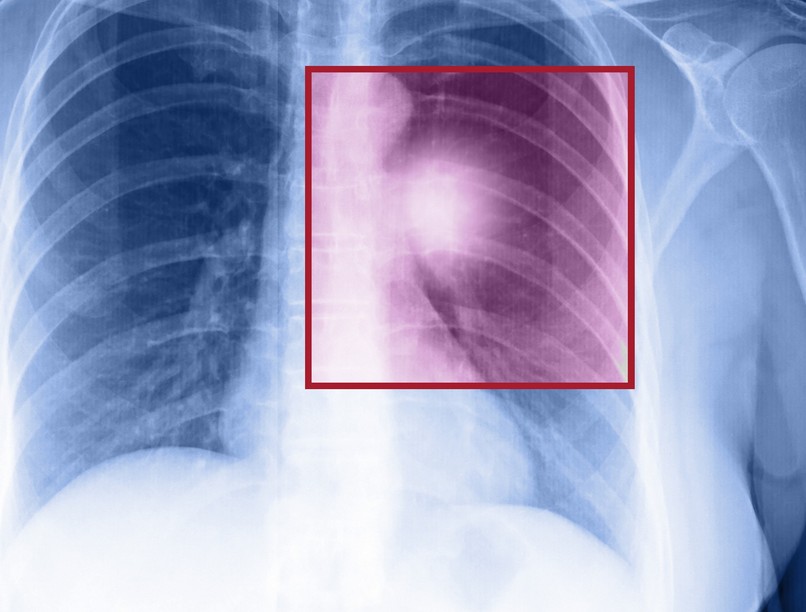

Rosszindulatú tüdődaganat: ezekkel a vizsgálatokkal mutatható ki a legjobban

Rosszindulatú tüdődaganatt diagnózis, tünet

Ahogy az összes daganatnál, itt is fontos, hogy mielőbb felismerésre kerüljön a betegség.

Európában lakosságarányosan Magyarországon halnak meg a legtöbben rosszindulatú tüdőrák miatt. Az alacsony sugárterhelésű tüdő CT-vizsgálatok jelentősen csökkenthetnék a tüdőrákban elhunytak számát.

Fontos, hogy a betegség szűrése alacsony sugárterhelésű tüdő CT-vizsgálattal történjen, hiszen a klasszikus mellkas röntgenvizsgálat az eseteket nagy részében nem ad megfelelő képet az elváltozások biztos felismeréséhez. Sokakban felvetődik a kérdés, hogy mennyire kockázatosak ezek a tüdő CT vizsgálatok, hiszen a computer tomográfia (CT) röntgensugarat használ, amely szintén rákkeltő lehet.